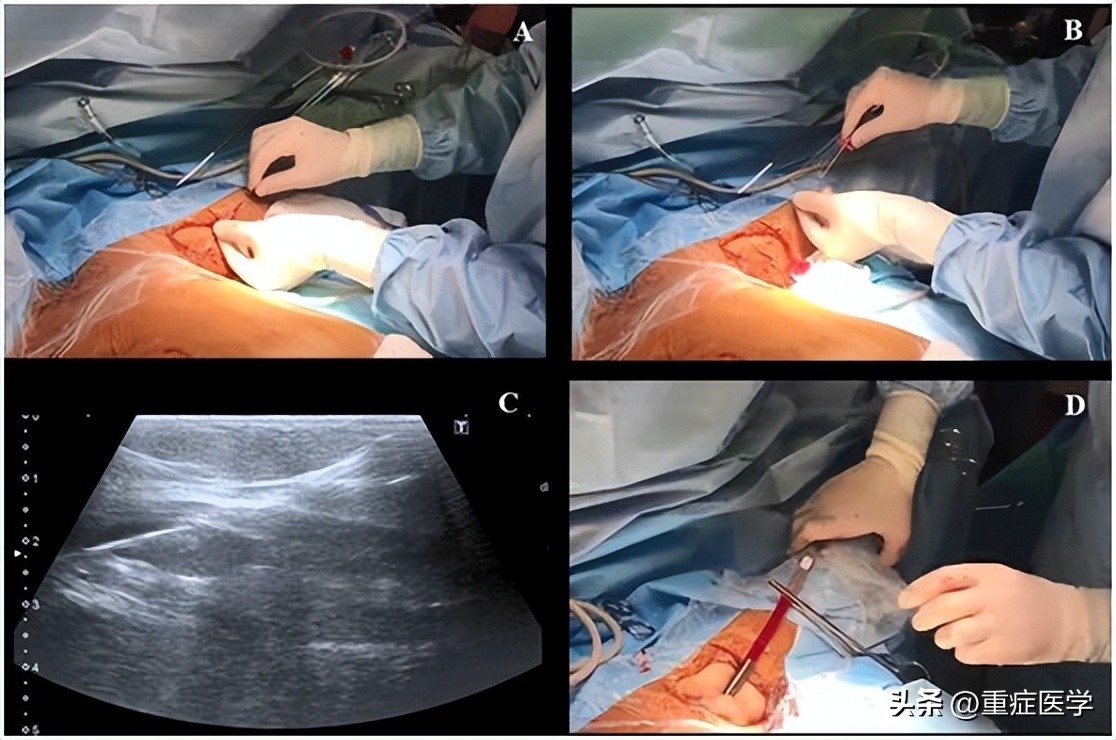

第三步,操作者左手持超声探头,右手持带穿刺针的注射器在超声引导下对腋静脉进行穿刺,超声长轴图像平面内同时可见静脉腔及穿刺针(图2)。皮肤穿刺点尽可能靠近超声探头远端的短边上。当穿刺针触碰到静脉前壁时,在压力的作用下,静脉壁会出现下沉塌陷,因此,此时应快速进针。

当在腋静脉腔内观察到针尖的斜面时(一个白点),可以很容易地确定穿刺针在血管内的位置(图2C)。也可以通过回抽血液1-2ml来确认穿刺针的位置是在静脉内。当患者血压较低时,无搏动性血流出现并不能排除穿刺到动脉的可能。随后置J形导丝,导丝的位置也可能在超声实时下确认(图3,A-C)。也可以通过颈部超声探查来排除导丝进行左侧颈内静脉。导丝置入长度应限定在20cm,以避免引起心律失常。随后扩张皮肤穿刺点,用Seldinger技术置入导管。在输注任何液体之前,回抽确认导管远端是否在血管腔内,随后再用肝素盐水冲洗导管。导管置入深度为20cm。

图2,A 沿超声探头长轴插入穿刺针;B 超声视窗下可见穿刺针进行静脉;C 超声视窗下看到的血管内穿刺针斜面。

图3,A和B置入导丝,C超声视窗下可见静脉的导丝;D 把导管固定